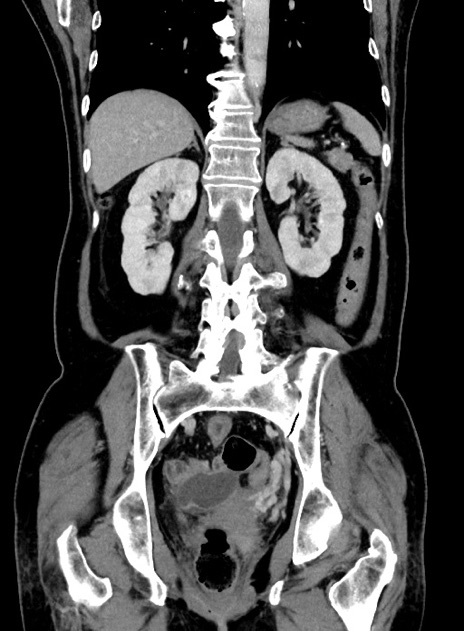

症例9(冠状断像)

【症例】 60歳代女性

【主訴】むかつき、みぞおちの痛み

【現病歴】3日前よりむかつきがあり、食事がとれない。

【既往歴】糖尿病

【身体所見】発熱なし、心窩部圧痛軽度あるも、腹膜刺激症状なし。

【データ】WBC 7400、CRP 1.92